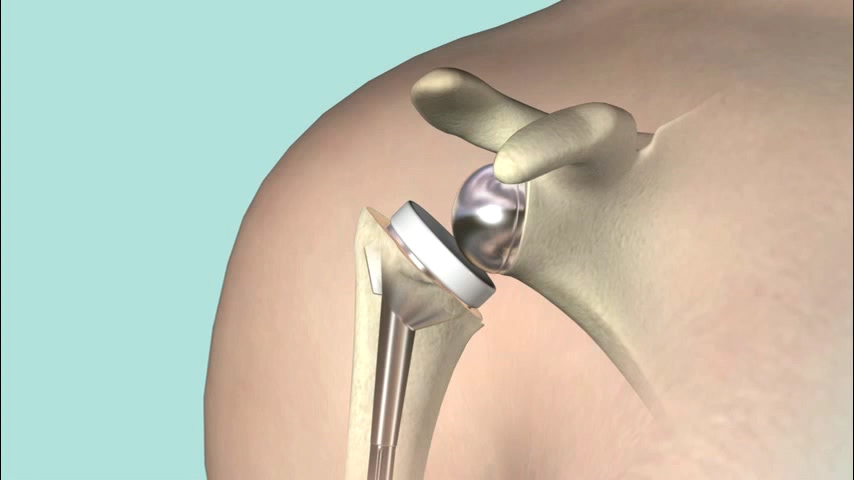

위의 사진과 같이 기존의 인공관절은 humerus 의 골두를 제거하고 glenoid 모습과 비슷하게 작동하는 원리로 인공관절이 되었으나 최근에는 humerus head 의 medialization 효과와 deltoid muscle lever arm의 증가로 더 효과가 있는 reverse shoulder arthroplasty 가 많이 시행되고 있습니다. 1990년대부터 수술을 시작했으니 30년 정도 지난 수술법입니다.

쉽게 생각하면 Convex 와 Concave가 반대로 된 구조라고 생각하면 됩니다. 회전의 중심(Center Of Motion)이 좀더 아래와 안쪽에 위치한 생역학적 장점을 갖고 있습니다.